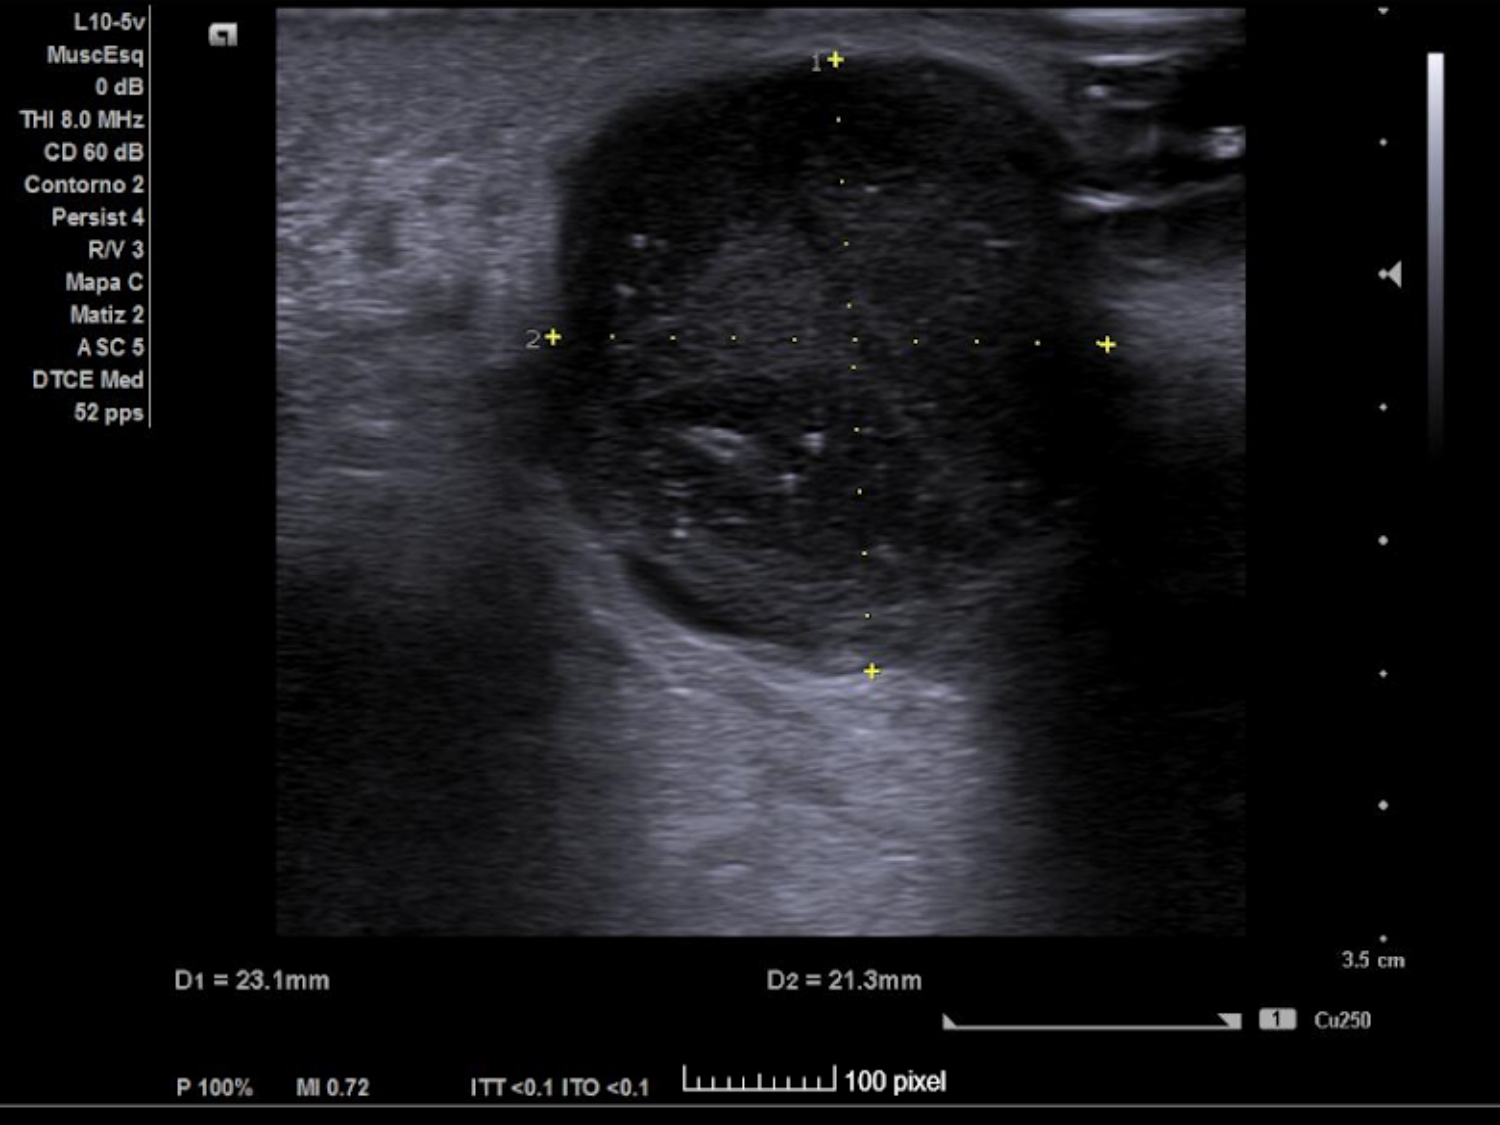

Se realiza ECO POCUS en la que se aprecia un absceso de 23 x 21 mm a menos de 1 cm de profundidad, con fácil acceso a nivel cutáneo y contenido heterogéneo, más anecoico en algunas zonas y poco tabicado.